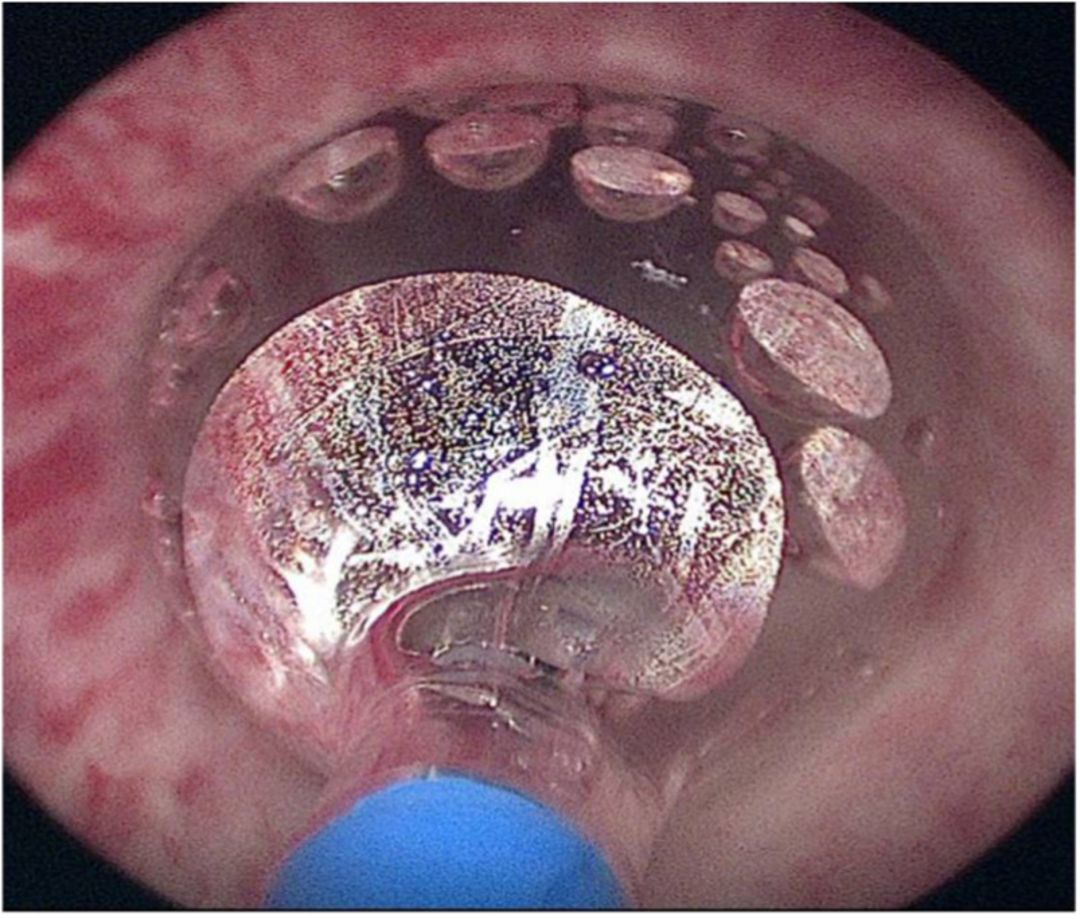

Figure 2 Optilume dilation